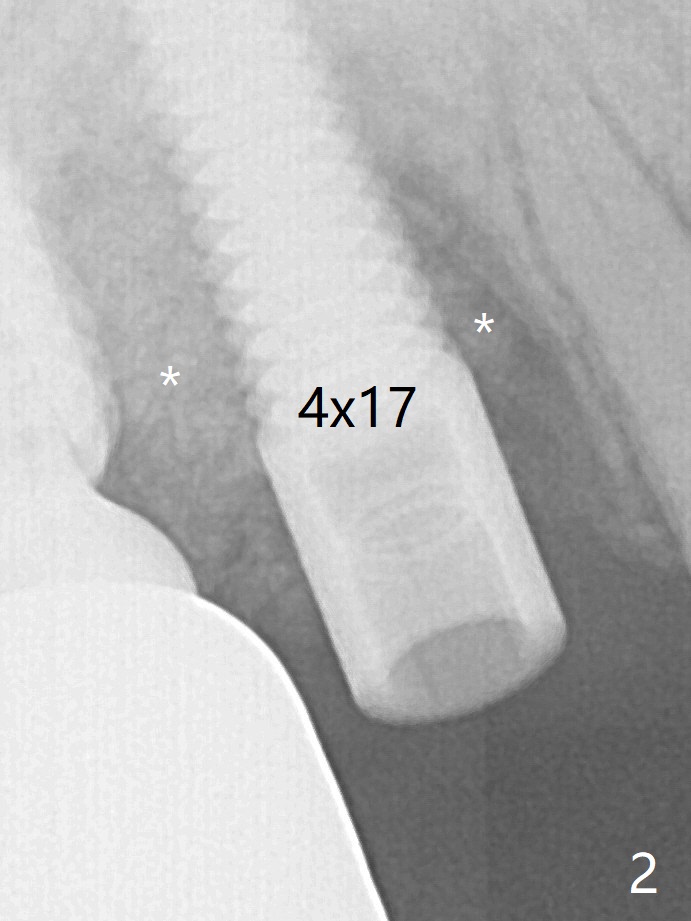

A 4x14 mm dummy implant is placed free hand (Fig.1). Following initial placement of a final 4x17 mm implant and bone graft (Fig.2 *), the crown and abutment of #3 and the guide are reseated for correct implant trajectory. The guide has to be removed for final depth control of the tissue-level implant. More bone graft is inserted mesial of #4 implant with a 3.5x5 mm abutment (Fig.3 *). The implant at # 4 seem to have osteointegrated, especially mesial, nearly 5.5 months postop (Fig.7,8).